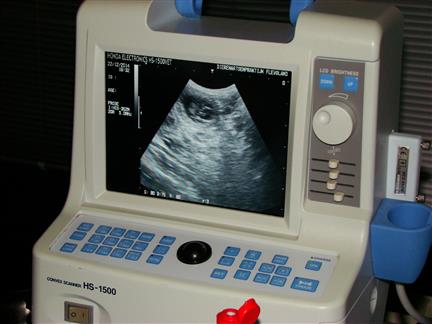

| 22 december 2014, eindelijk is het dan zo ver, 28 dagen na de dekking, dus tijd voor de echo om te kijken of Fleur drachtig is |

| na het scheren ligt Fleur braaf op haar rug, met onze dochter aan de ene kant en de assistente aan de andereke kant, en dan de eerste beelden, wat een mooi gezicht :-) |